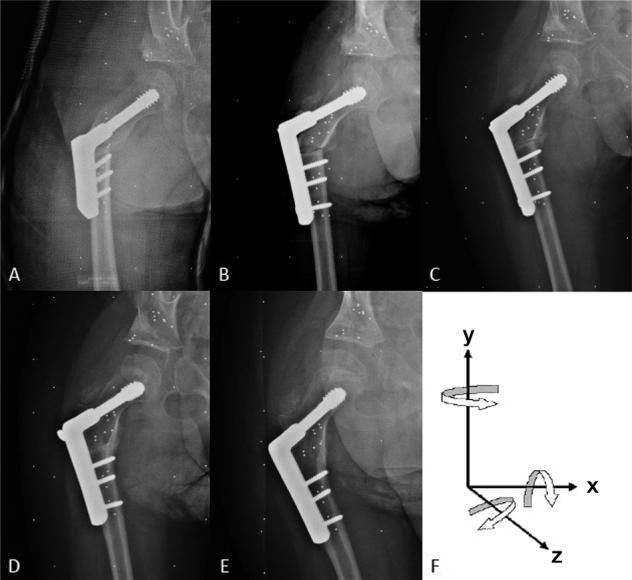

Background and purpose - Studies have indicated that one-third of children with cerebral palsy (CP) develop dislocation of the hip that needs surgical intervention. When hip dislocation occurs during childhood surgical treatment consists of tenotomies, femoral varus derotation osteotomy (VDRO), and acetabuloplasty. Relapse is observed in one-fifth of cases during adolescence. In this prospective cohort study, we performed a descriptive evaluation of translation and rotation across VDROs in children with neuromuscular disorders and syndromes by radiostereometric analysis (RSA). We assessed "RSA stability" and migration across the VDROs. Patients and methods - Children with a neuromuscular disorder were set up for skeletal corrective surgery of the hip. RSA follow-ups were performed postoperatively, at 5 weeks, and 3, 6, and 12 months after surgery. Results - 27 femoral VDROs were included; 2 patients were excluded during the study period. RSA data showed stability across the VDRO in the majority of cases within the first 5 weeks. At the 1-year follow-up, the mean translations (SD) of the femoral shaft distal to the VDRO were 0.51 (1.12) mm medial, 0.69 (1.61) mm superior, and 0.21 (1.28) mm posterior. The mean rotations were 0.39° (2.90) anterior tilt, 0.02° (3.07) internal rotation, and 2.17° (2.29) varus angulation. Interpretation - The migration stagnates within the first 5 weeks, indicating stability across the VDRO in most patients.

背景与目的——研究表明,三分之一的脑瘫患儿会发生髋关节脱位,需要手术干预。儿童期发生髋关节脱位时,手术治疗包括肌腱切断术、股骨内翻旋转截骨术(VDRO)和髋臼成形术。青春期有五分之一的病例会出现复发。在这项前瞻性队列研究中,我们通过放射立体测量分析(RSA)对神经肌肉疾病和综合征患儿的VDRO手术中的平移和旋转进行了描述性评估。我们评估了VDRO手术中的“RSA稳定性”和移位情况。

患者与方法——患有神经肌肉疾病的儿童准备接受髋关节骨骼矫正手术。术后、术后5周以及术后3、6和12个月进行RSA随访。

结果——纳入27例股骨VDRO手术;研究期间排除2例患者。RSA数据显示,在最初5周内,大多数病例的VDRO手术具有稳定性。在1年随访时,VDRO远端股骨干的平均平移(标准差)为内侧0.51(1.12)mm、上方0.69(1.61)mm和后方0.21(1.28)mm。平均旋转角度为前倾0.39°(2.90)、内旋0.02°(3.07)和内翻成角2.17°(2.29)。

解读——移位在最初5周内停滞,表明大多数患者的VDRO手术具有稳定性。